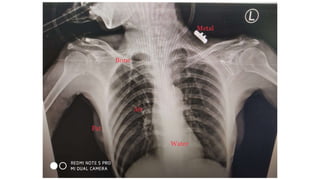

Relative Densities:

• The hierarchy of relative densities from least dense (Black) to most

dense (white) :

• Gas (air in the lungs)

• Fat (fat layer in soft tissue)

• Water (same density as heart and blood vessels)

• Bone (the most dense of the tissues)

• Metal (foreign bodies)

Relative Densities: • Thehierarchy of relative densities from least dense (Black) to most dense (white) : • Gas (air in the lungs) • Fat (fat layer in soft tissue) • Water (same density as heart and blood vessels) • Bone (the most dense of the tissues) • Metal (foreign bodies)